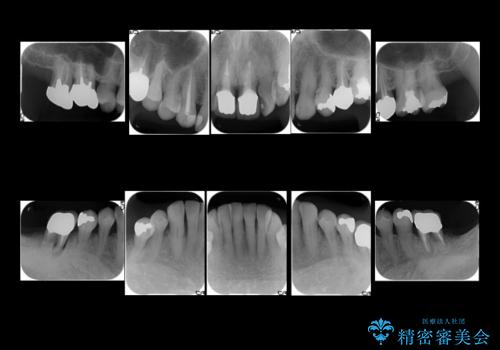

- 右下の奥歯が割れてしまい、抜歯を行いました。

ブリッジにできない位置であったため、インプラントでかめるようにしました。

また、向かい合う上の歯が挺出(伸び出してしまうこと)しており、インプラントを入れることが難しかったため、長さを短くかぶせ治しました。

また、上顎前歯以外の根の治療のやり直しを行いました。

上顎前歯は他院で根管治療とセラミックを行なったとのことで、歯肉縁下形成のため、歯肉の腫れが治りにくい状況でしたがやり直しは希望されませんでした。

左下に関しては、経過観察を行い、歯が割れたりした場合にインプラントを考えることになりました。